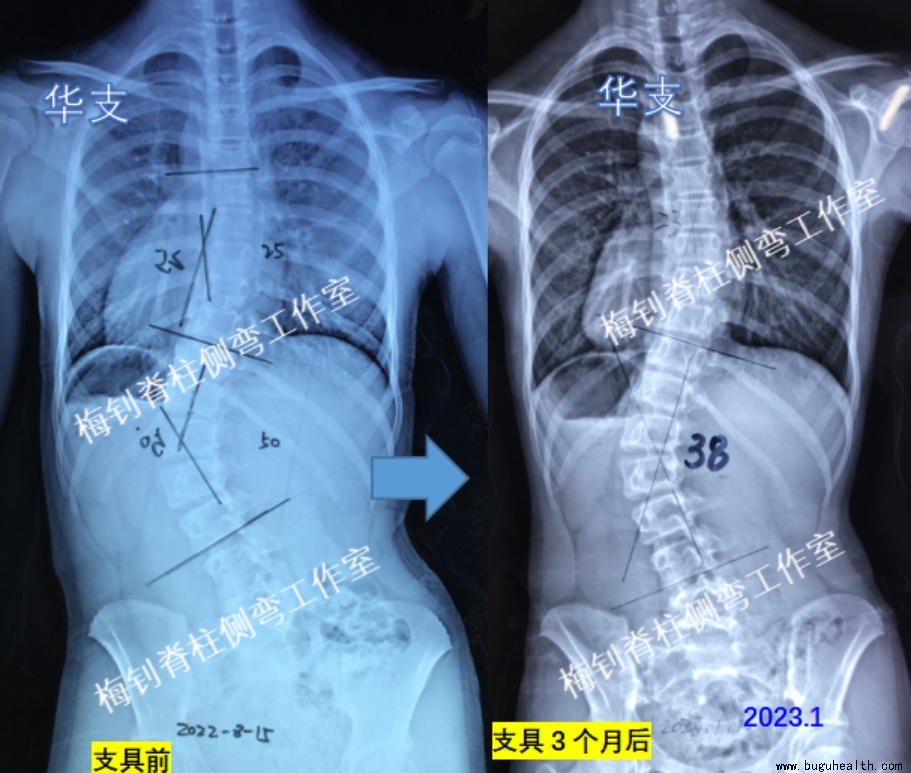

案例5

女孩,2019年发现侧弯,当时只有14度,后逐渐发展,至2022年8月,主弯曲达到了50度。10月份来我工作室定制支具,13周岁。

因家长比较着急,穿戴支具3个月后就脱支具48小时拍了X光片,主弯曲由50度恢复至38度。体表也有明显好转。期间身高增加3cm。希望患儿能够继续坚持,期待有更好的效果!